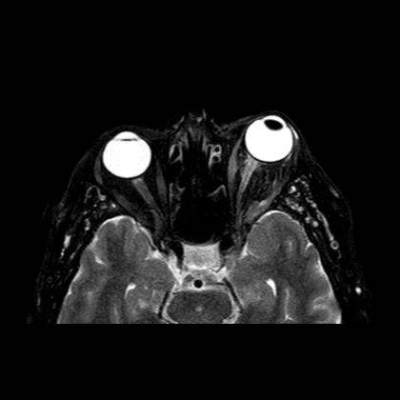

- A) Orbital MRG’de yağ baskılı T2A görüntülerde sol orbital globta ekzoftalmus (ok) izlenmiş olup retrobulbar yağlı dokuda kirlenmeler (ok) ve dilate superior oftalmik ven (ok) dikkati çekiyor. Beyin MRG’de kontrastlı T1A görüntüde sol kavernöz sinüste simetriğine oranla genişleme (ok) izleniyor.

- B) Pre ve post-kontrast yağ basklılı T1A görüntüler incelendiğinde superior oftalmik venin (oklar) kontrast madde verildikten sonra homojen dolum gösterdiği, dilate ve tortiyoze görünümde olduğu izleniyor.

- BT ve MRG: Propitozis, ekstraokuler kaslarda genişleme, superior oftalmik vende genişleme ve tortiyozite, ipsilateral kavernöz sinüste genişleme gösterilebilir. Serebral venöz konjesyonu olan ve intrakraniyal basınçları yükselen hastalarda serebral ödem, hemoraji, leptomeningeal ve kortikal venlerin dilastasyonunu görülebilir. Bunlara ek olarak travmaya sekonder olgularda BT ile eşlik eden fraktürler gösterilebilir.